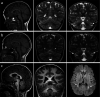

TRPM3 is a temperature- and neurosteroid-sensitive plasma membrane cation channel expressed in a variety of neuronal and non-neuronal cells. Recently, rare de novo variants in TRPM3 were identified in individuals with developmental and epileptic encephalopathy, but the link between TRPM3 activity and neuronal disease remains poorly understood. We previously reported that two disease-associated variants in TRPM3 lead to a gain of channel function . Here, we report a further 10 patients carrying one of seven additional heterozygous TRPM3 missense variants. These patients present with a broad spectrum of neurodevelopmental symptoms, including global developmental delay, intellectual disability, epilepsy, musculo-skeletal anomalies, and altered pain perception. We describe a cerebellar phenotype with ataxia or severe hypotonia, nystagmus, and cerebellar atrophy in more than half of the patients. All disease-associated variants exhibited a robust gain-of-function phenotype, characterized by increased basal activity leading to cellular calcium overload and by enhanced responses to the neurosteroid ligand pregnenolone sulfate when co-expressed with wild-type TRPM3 in mammalian cells. The antiseizure medication primidone, a known TRPM3 antagonist, reduced the increased basal activity of all mutant channels. These findings establish gain-of-function of TRPM3 as the cause of a spectrum of autosomal dominant neurodevelopmental disorders with frequent cerebellar involvement in humans and provide support for the evaluation of TRPM3 antagonists as a potential therapy.